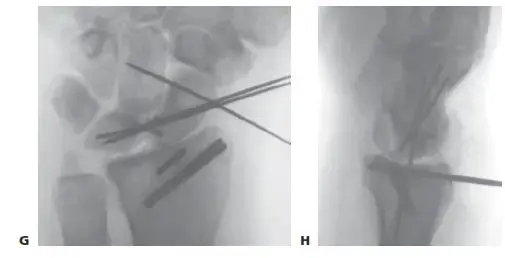

صفحة 1 من 2تعرف على كسور الكوع أوليكرانون: الأسباب، الأعراض، وطرق العلاج الفعالة